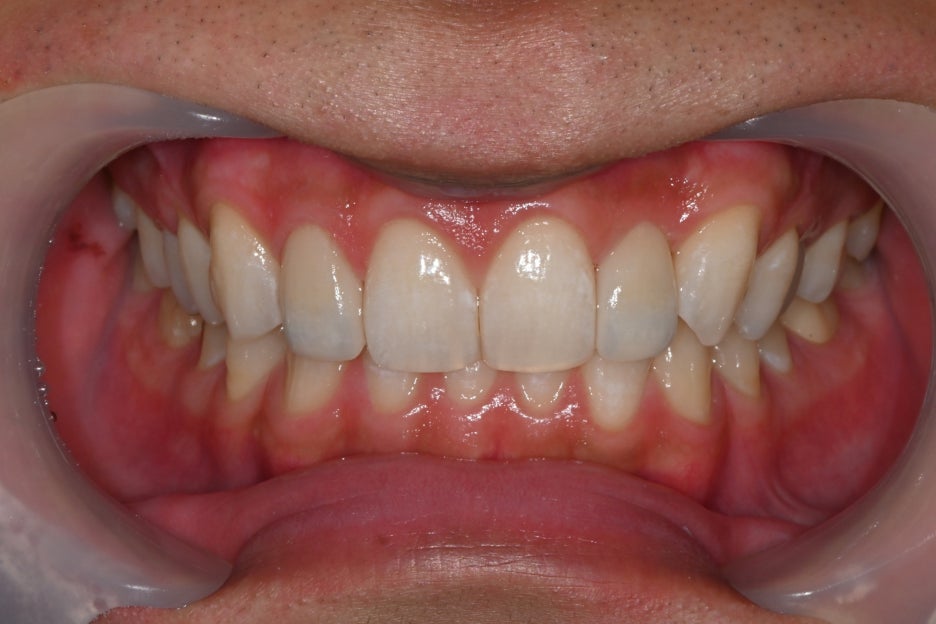

< BEFORE & AFTER >

1-week follow-up after treatment

Object Zero Laminate

At the one-week prosthetic check as well,

Object Zero Laminate is designed so that the gum line and the prosthetic margin

flow together naturally,

so there is less lifting over time and a very low risk of discoloration.